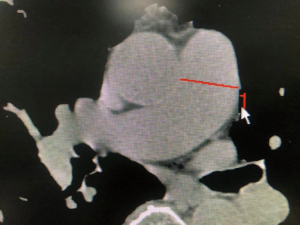

Chest CT in our study was performed on patients during their first admissions within the first three days, patient in supine position and images taken in inspiration were used in this study. Two pulmonologists independently measured the MPAD and average of it was used in this study. The MPAD was measured on axial plane at the tubular site, widest diameter perpendicular to the short axis of pulmonary artery (Figure 1). Moreover, the interobserver reliability was assessed by calculating intraclass correlation coefficients (ICCs). Other data of significant pneumonic changes and interstitial pneumonic changes were also noted down. We were only able to retrieve height and weight of 96 patients from our records and mean and standard deviation of body mass index (BMI) and body surface area (BSA) were calculated from these data.